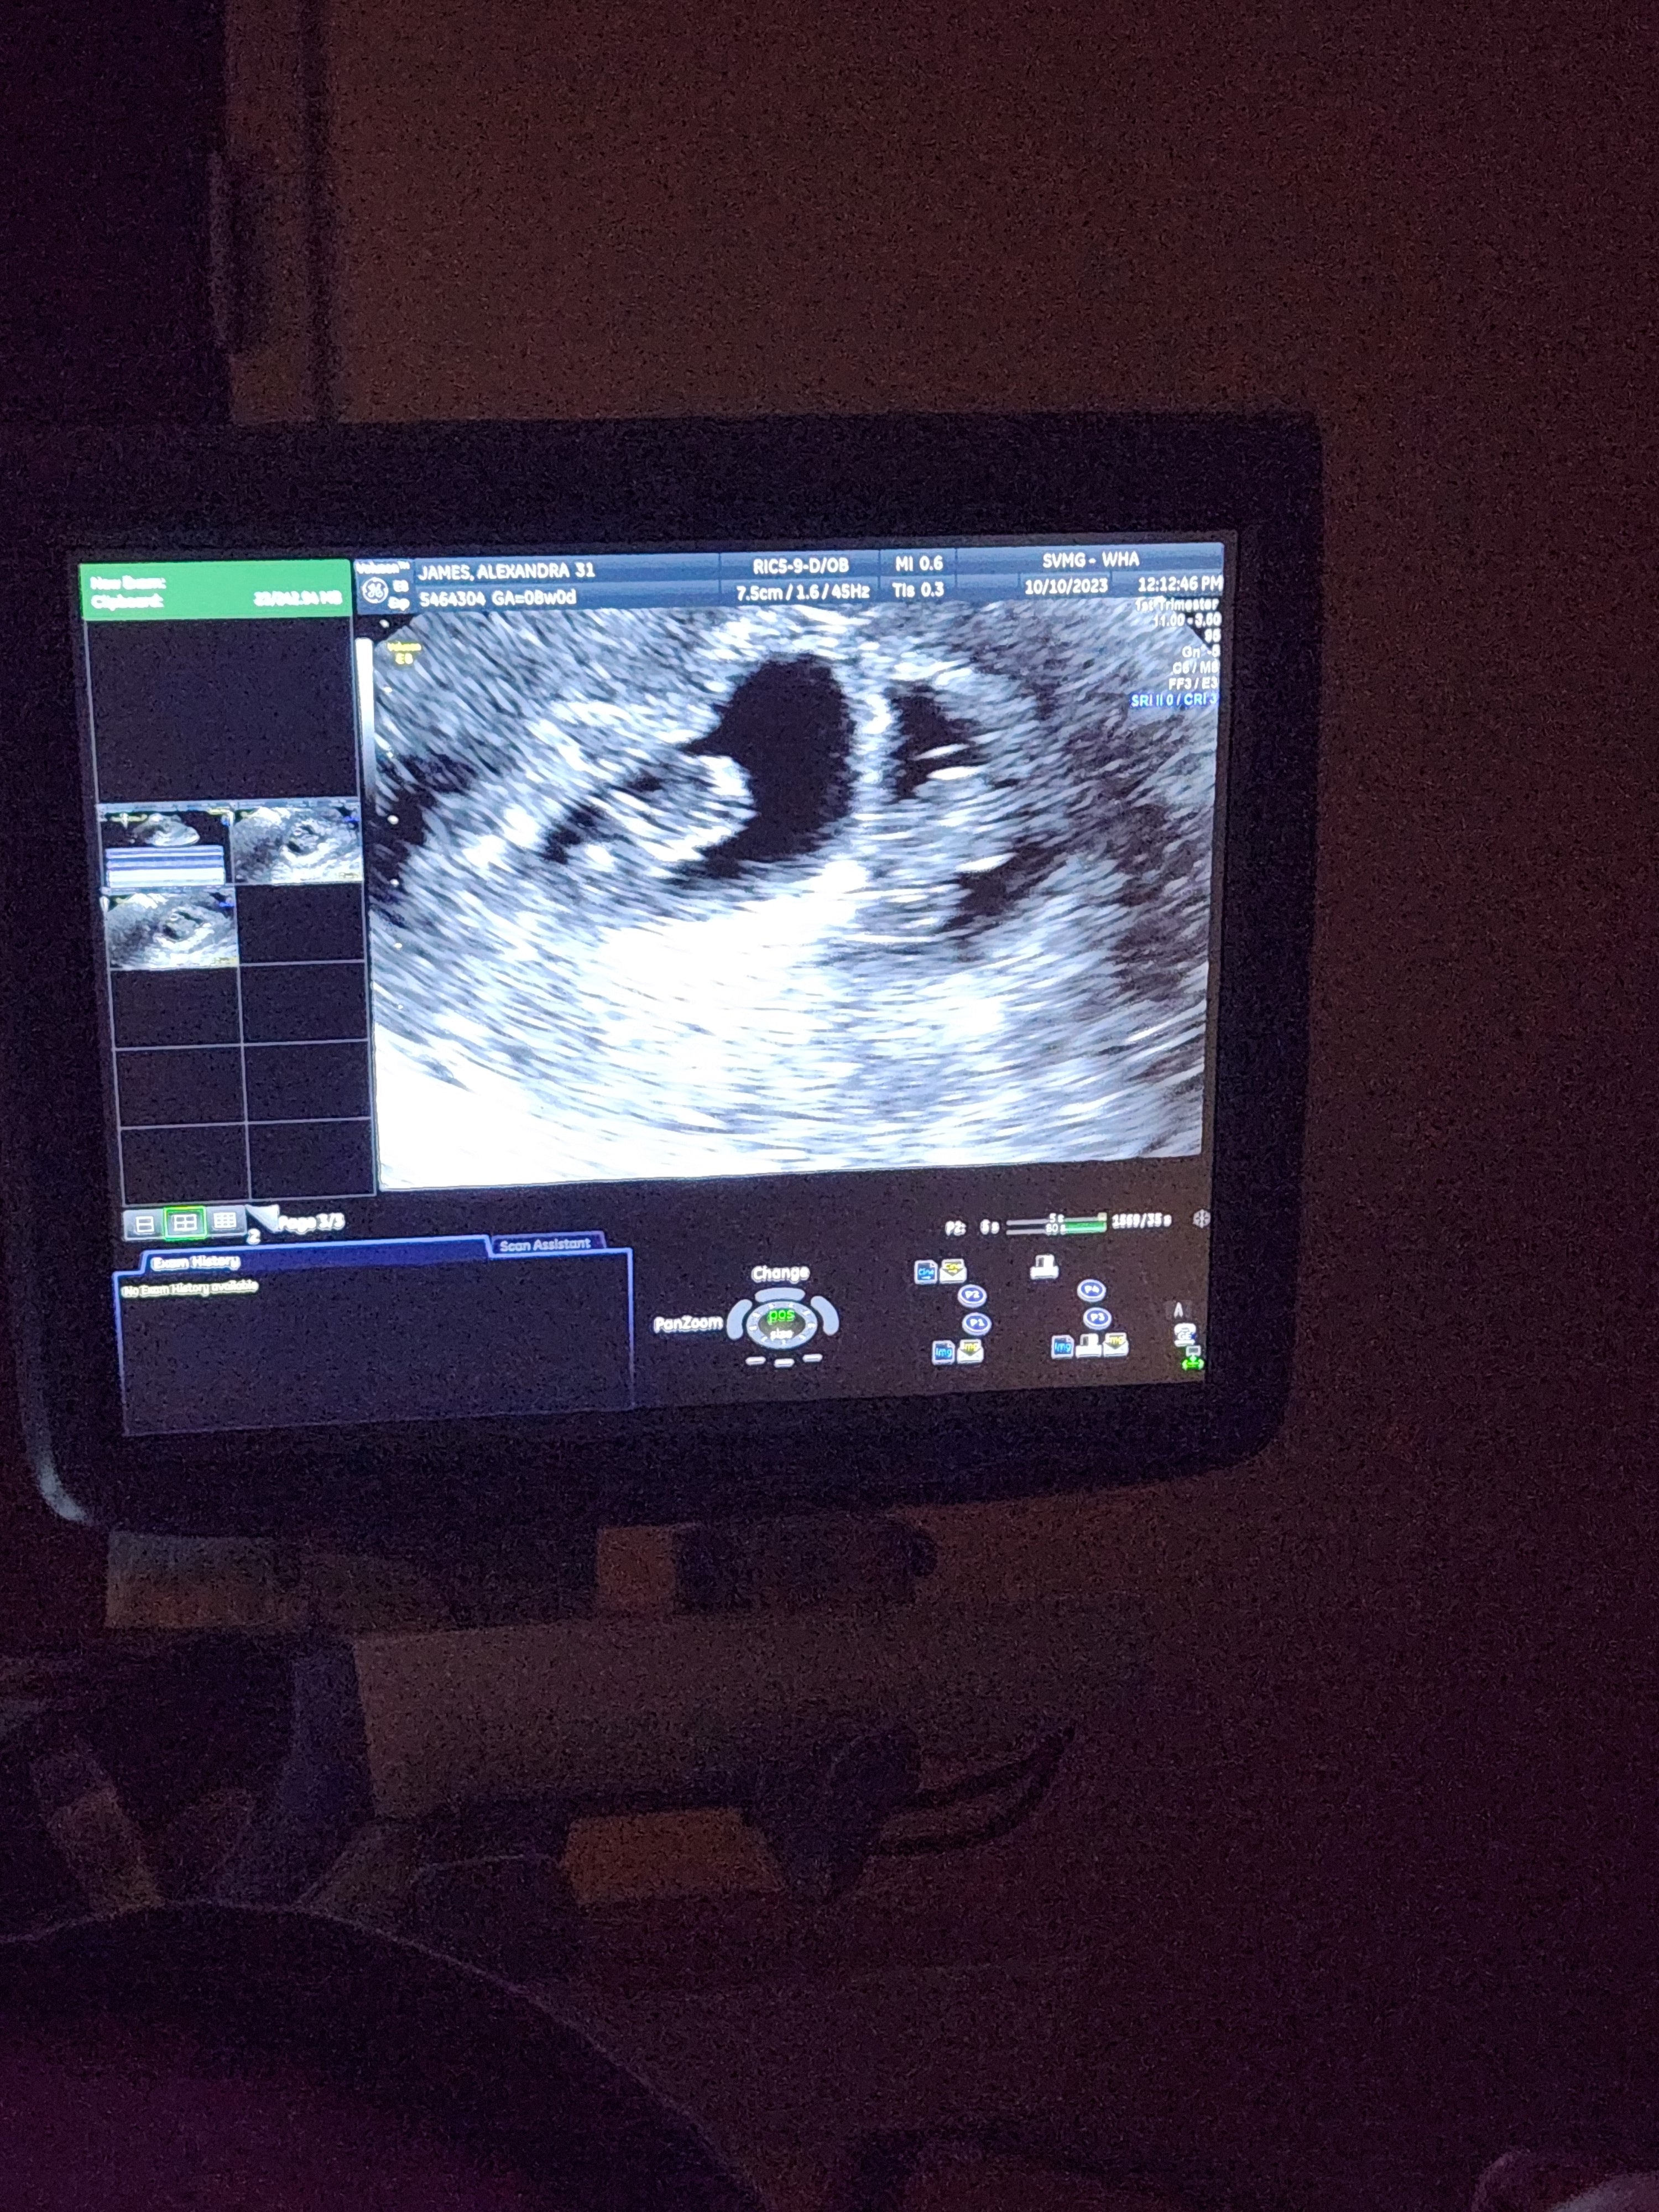

We had been trying for 9 months to have a baby and stumbled upon Mosie baby on TikTok. We talked about it for a few weeks and finally decided to give it a try. We used it once and were able to conceive a child. At our 8 week ultrasound we found out we're expecting twins and are so excited for the new journey!